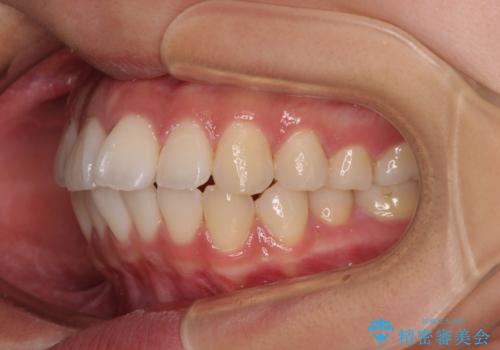

- 前歯が突出して、眠るときに口が開いてしまうことを気にして来院された患者様です。

横から見た際の口元の飛び出した印象も改善したいとのことで、上下左右の第一小臼歯4本を抜歯し、ワイヤー装置にて抜歯矯正を行うこととしました。

舌の突出癖改善のためのトレーニングをしっかりと実践してくださり、2年強の治療期間でしっかりと仕上げることができました。